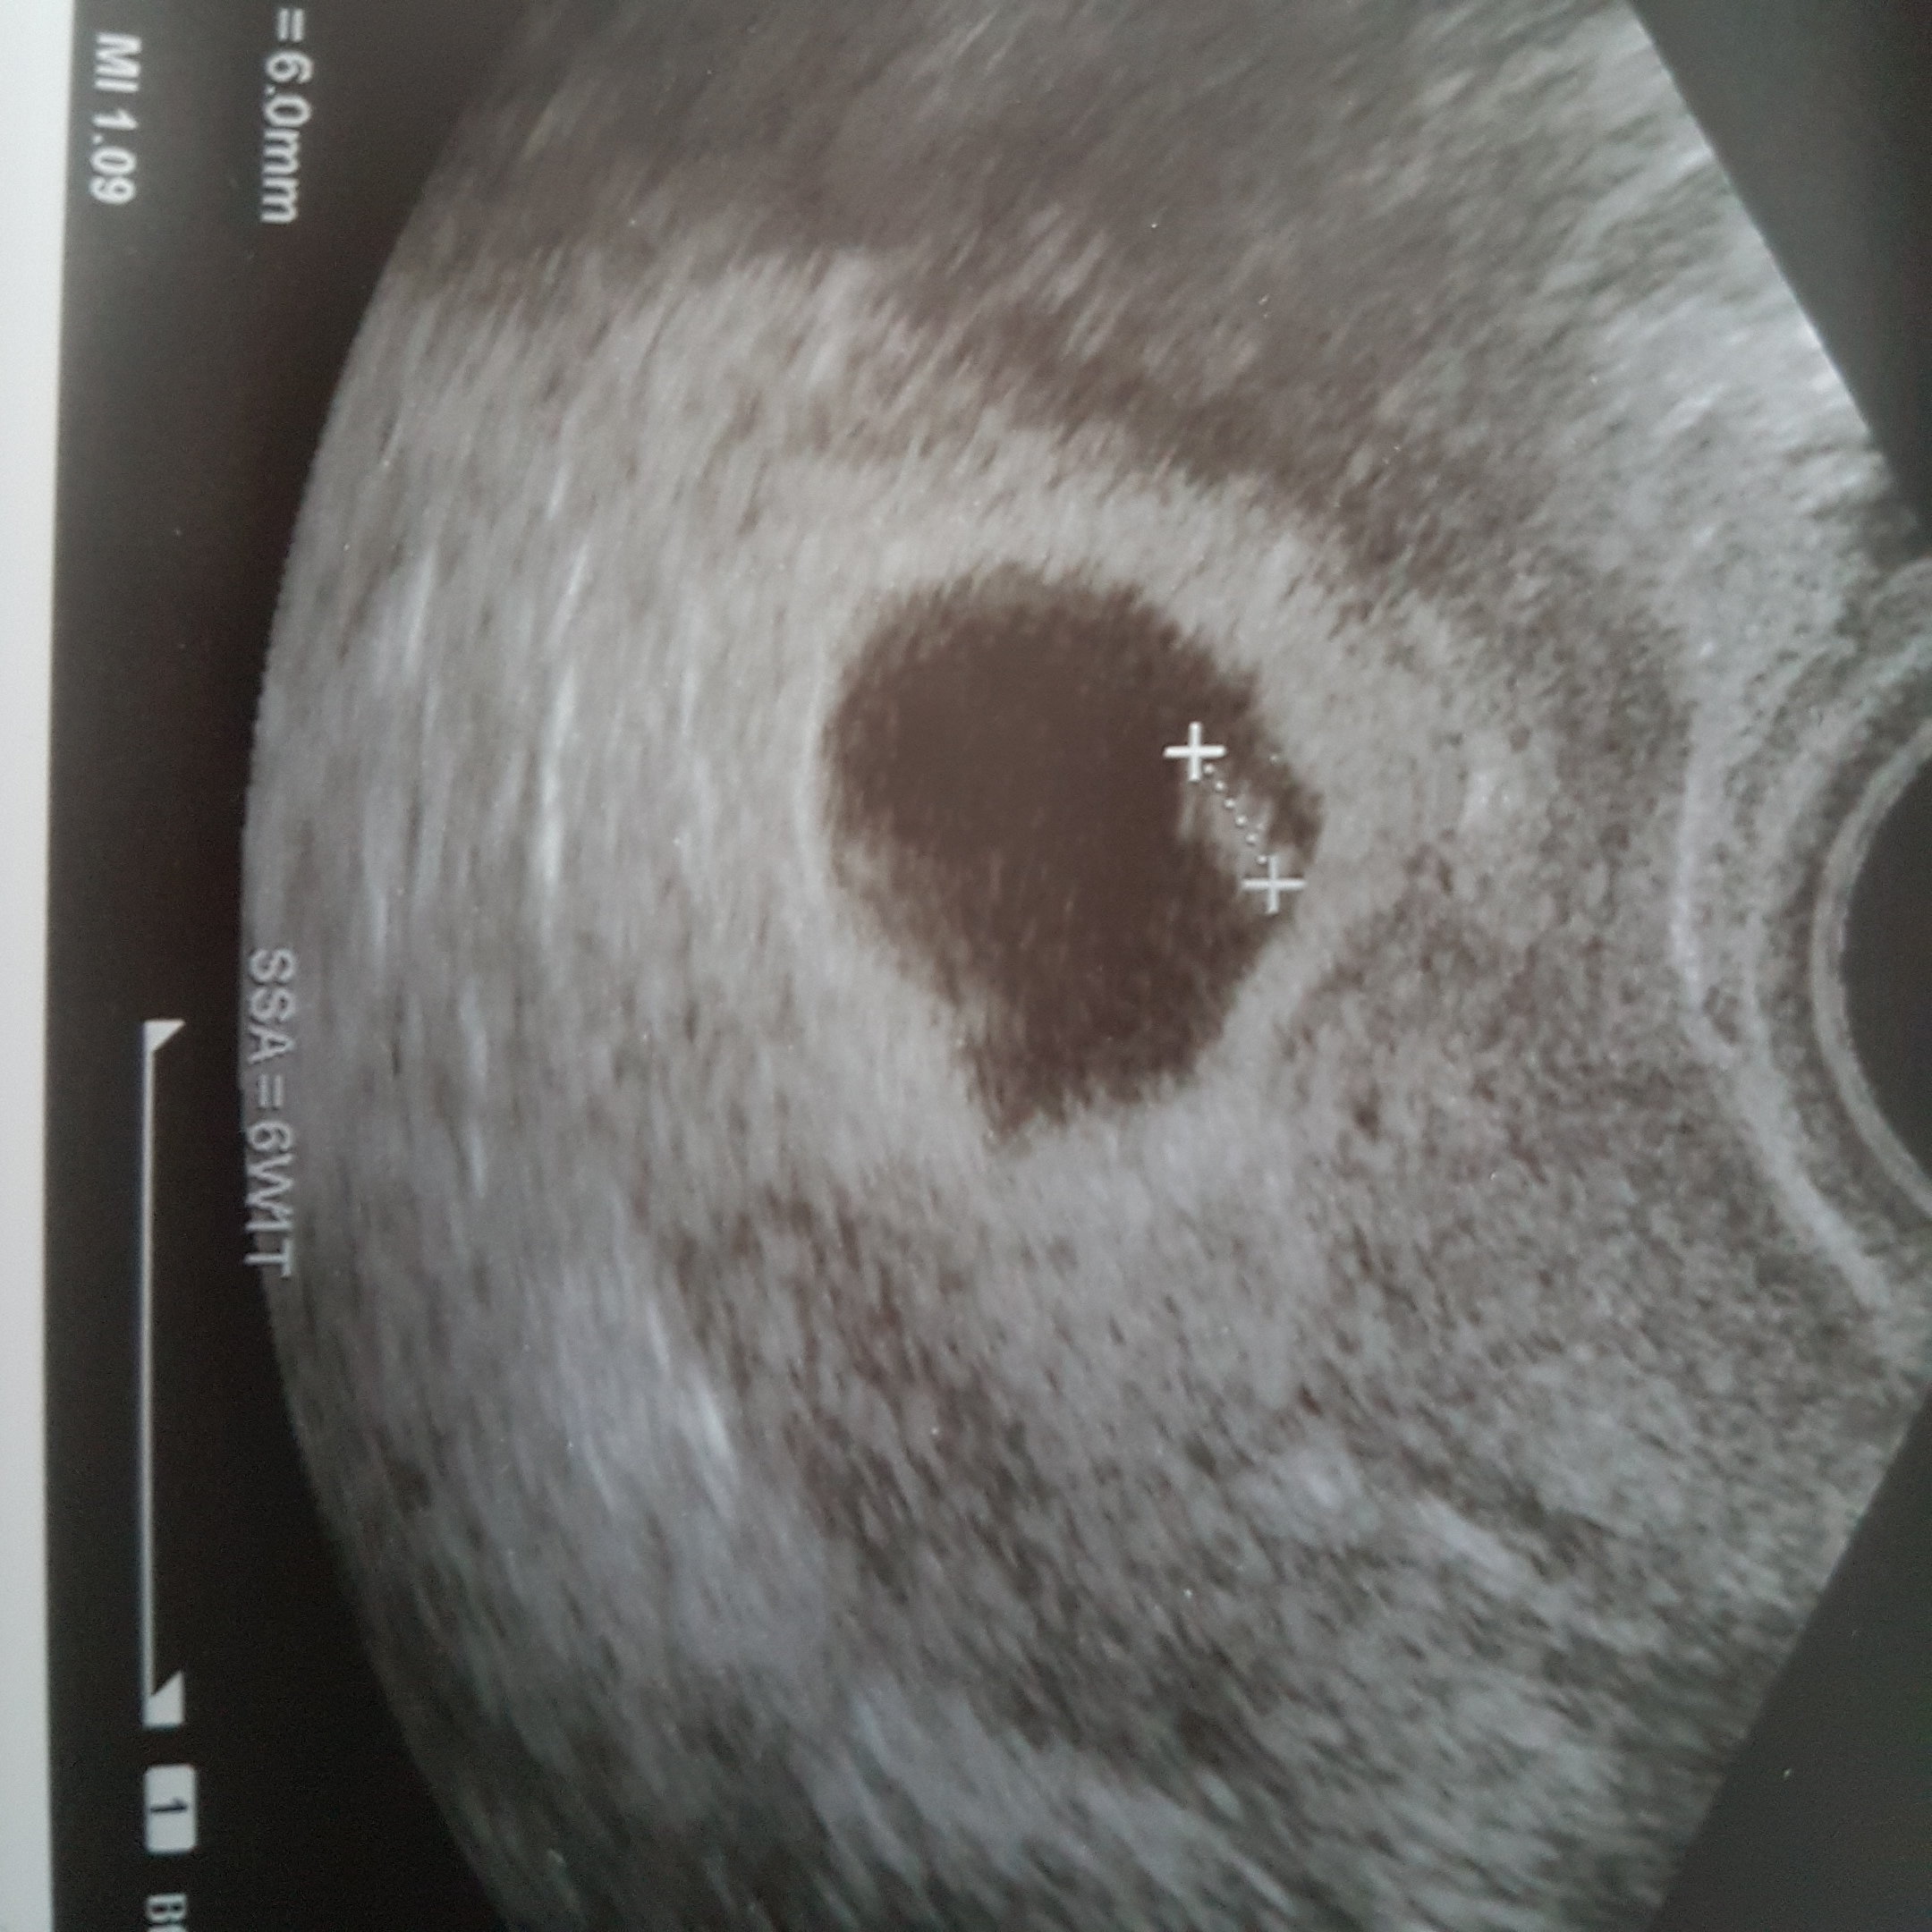

To i ja sie pochwale. Nareszcie cos widac. Ma juz ma całe 6mm

Serduszko tez biło takze wszystko dobrze.